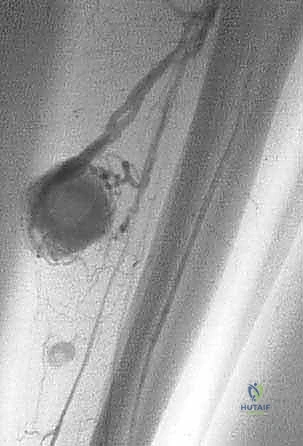

- الرنين المغناطيسي (MRI): هو المعيار الذهبي (Gold Standard) لتقييم الأورام. يوضح بدقة امتداد الورم في النخاع العظمي والأنسجة الرخوة، وعلاقته بالأعصاب والأوعية الدموية.

لضمان أخذ العينة من الجزء الأكثر تمثيلاً للورم وتجنب المناطق الميتة (Necrotic areas)، يستخدم الدكتور هطيف جهاز الأشعة المقطعية أو جهاز القوس المفلور (C-arm) لتوجيه الإبرة في الوقت الفعلي.

الحالة الأولى: إنقاذ ركبة رياضي شاب

شاب يبلغ من العمر 19 عاماً عانى من ألم مستمر في الركبة وتورم لم يستجب للمسكنات. بعد الفحص السريري الدقيق وإجراء الرنين المغناطيسي، اشتبه الأستاذ الدكتور محمد هطيف بوجود ورم. تم إجراء خزعة إبرة أساسية دقيقة جداً. أظهرت النتائج وجود "ساركوما عظمية" في مراحلها الأولى. بفضل الخزعة الدقيقة التي لم تلوث الأنسجة المحيطة، تمكن الدكتور هطيف لاحقاً من استئصال الورم بالكامل وتركيب مفصل صناعي خاص بالأورام، مما أنقذ ساق الشاب من البتر ومكنه من العودة للمشي بشكل طبيعي.